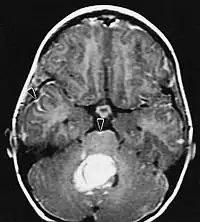

Sur-L'IRM montre une tumeur intracrânienne comme une lésion massive qui peut devenir plus luminescente après utilisation du produit de contraste. Cependant, il y a toujours une anomalie de signal dans -L'imagerie par résonance magnétique, qui indique la présence d'une néoplasie ou d'un œdème vasogénique. Habituellement, une luminescence accrue (amélioration du contraste) indique une tumeur d'un grade supérieur de malignité. Un anneau de contraste est caractéristique du glioblastome, avec la partie luminescente correspondant à la partie vitale de la tumeur maligne, et la plus foncée - zone hypointense correspondant à une nécrose tissulaire.

Glioblastome

Les tumeurs des cellules gliales les plus courantes et les plus malignes sont les glioblastomes. Ils consistent en une masse hétérogène de cellules d'astrocytome peu différenciées principalement chez l'adulte. Ils surviennent généralement dans les hémisphères cérébraux, plus rarement dans le tronc cérébral ou la moelle épinière. Sauf dans de très rares cas, comme toutes les tumeurs cérébrales, elles ne s'étendent pas au-delà des structures du système nerveux central.

Le glioblastome peut provenir d'une forme diffuse (II. grade) ou un astrocytome anaplasique (III. grade) développer. Dans ce dernier cas, il est dit secondaire. Cependant, lorsqu'elle survient sans antécédent ni signe de malignité antérieure, on parle de maladie primaire. Les glioblastomes sont traités par chirurgie, radiothérapie et chimiothérapie. Ils sont difficiles à guérir et rares sont les cas qui survivent au-delà de trois ans.